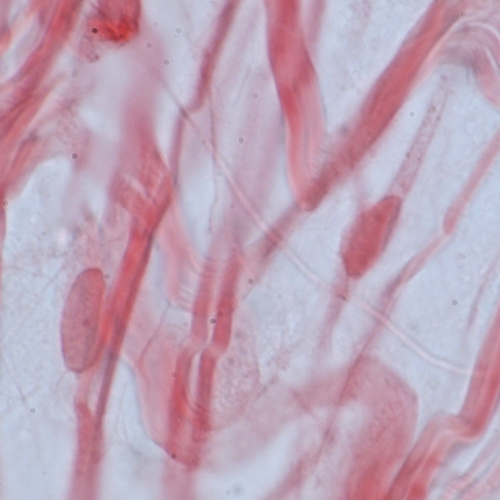

Differences among the connective tissues also depend on the three-dimensional organization of the molecular components. The type I collagen fibrils in tendon are packed into thick, parallel bundles of fibres, whereas type I collagen fibrils in skin are randomly oriented. In cortical bone, helical arrays of type I collagen fibrils are deposited around haversian canals. |